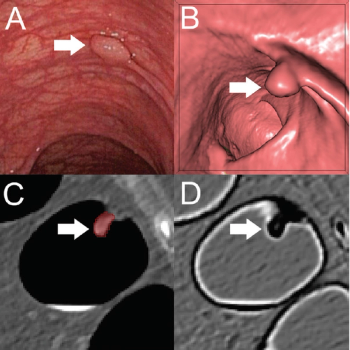

Implementing a radiomics-based machine learning algorithm allows CT colonography to differentiate between benign and pre-cancerous polyps with high sensitivity and specificity.